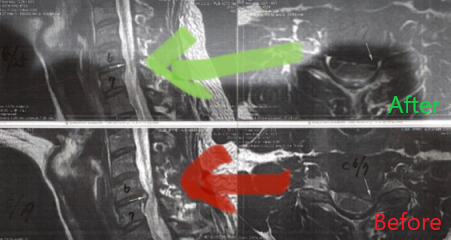

もちろん、症状の改善スピードは人それぞれです。症状が早くになくなっても、はじめにたてた施術計画に基づいて身体を改善してゆきます(身体を根本改善するため:元に戻らない身体にするため)。途中、MRIを新しくとることになり(病院の意向)、C6/C7のヘルニアがかなりひいていました。これは本人もびっくりしていました。

後日撮った新しいMRIでは、ヘルニアの突出部分も見事になくなっていました。